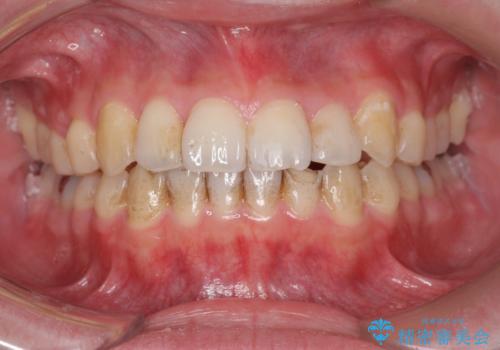

下の前歯が欠けている セラミックで審美的に エアフローで着色除去も

- 左下の前歯が削れて欠けているとのことで、治療希望されました。

プラスチックで詰めたものが度々取れてしまうとのこと。

しみないようであれば機能的にはそこまで問題はないと説明しましたが、審美的な治療をご希望でした。

プラスチックの詰め物と比較して、変色もなく、脱離もしにくいセラミッククラウンで修復しました。

前歯のステインはエアフローという方法で綺麗にクリーニングしています。